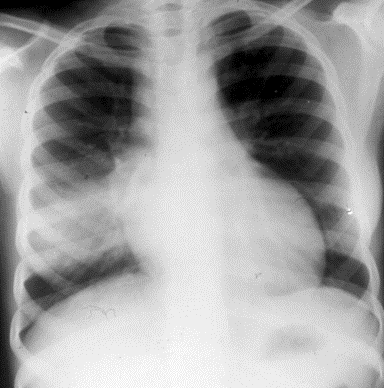

A 14-year-old girl with sickle cell anemia presents with 3 days of a persistent nonproductive cough, fever, malaise, anorexia and one day of right-sided pleuritic chest pain. Her physical examination is notable for a temperature of 39.7°C, a pulse of 110 beats/min, a respiratory rate of 22 breaths/min, and a BP of 110/60 mmHg. Dullness and inspiratory crackles are noted over the right middle lobe. Her neurologic exam is normal and she has no evidence of a sickle cell crisis. Her chest x-ray is shown below.